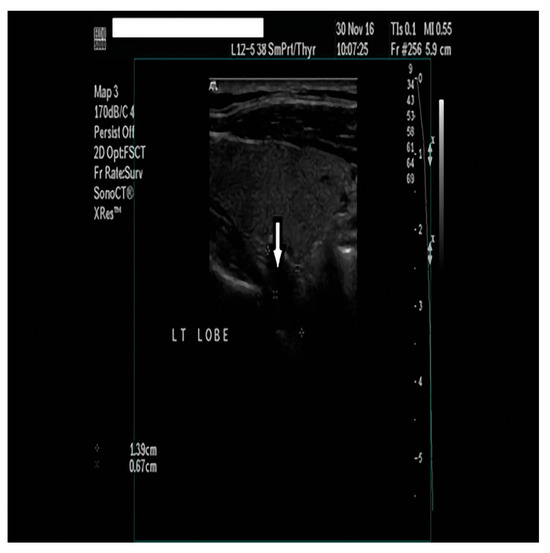

2. Case Presentation

2.1. Diagnostic Assessment